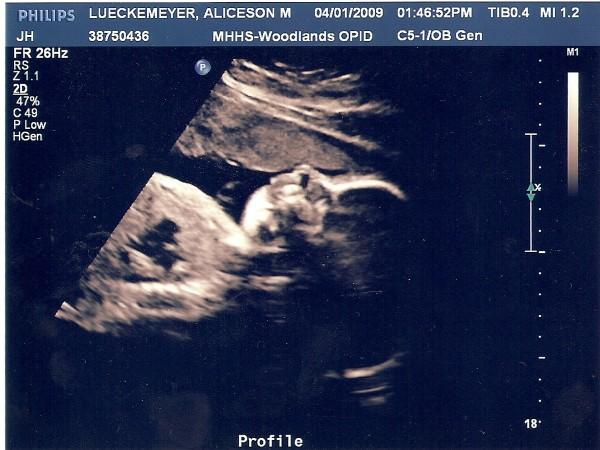

Ali